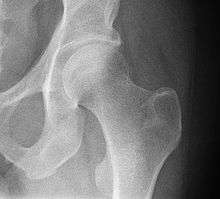

The hip joint is a synovial joint formed by the articulation of the rounded head of the femur and the cup-like acetabulum of the pelvis. It forms the primary connection between the bones of the lower limb and the axial skeleton of the trunk and pelvis. Both joint surfaces are covered with a strong but lubricated layer called articular hyaline cartilage. The cuplike acetabulum forms at the union of three pelvic bones — the ilium, pubis, and ischium.[5] The Y-shaped growth plate that separates them, the triradiate cartilage, is fused definitively at ages 14–16.[6] It is a special type of spheroidal or ball and socket joint where the roughly spherical femoral head is largely contained within the acetabulum and has an average radius of curvature of 2.5 cm.[7] The acetabulum grasps almost half the femoral ball, a grip augmented by a ring-shaped fibrocartilaginous lip, the acetabular labrum, which extends the joint beyond the equator.[5] The head of the femur is attached to the shaft by a thin neck region that is often prone to fracture in the elderly, which is mainly due to the degenerative effects of osteoporosis.

The acetabulum is oriented inferiorly, laterally and anteriorly, while the femoral neck is directed superiorly, medially, and slightly anteriorly.